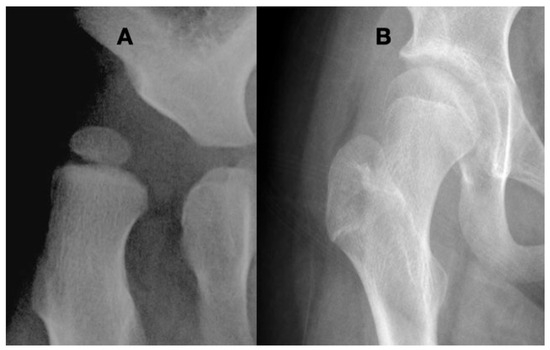

3.3.3. Pathology of Hip Development in Children with Low Tone and Muscle Weakness

4.1.2. Pathologic Role of Coxa Valga and the Impact of its Correction in Weak and Hypotonic Hips

4.1.3. Pathologic Role of Coxa Valga and Treatment Options in Paralytic Hips